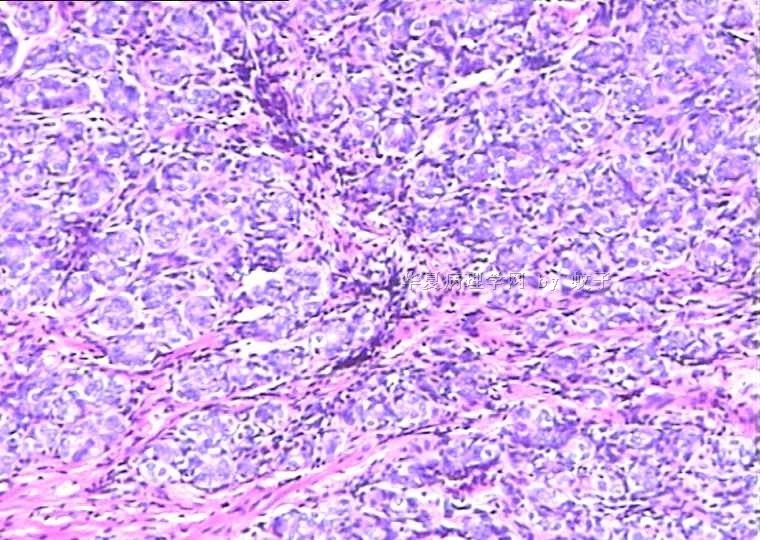

B2156乳腺活检

姓    名: ××× 性别:  女 年龄:  20

简要病史:  右乳包块8年。

肉眼检查:  灰白不整形组织一块,切面灰白,灰红,实性,质韧。

• 乳腺活检图4

图4

标签:乳腺腺病

旺识型腺病

有包膜吗?良性,首先考虑纤维腺瘤(图5、6透明变的纤维支持),其次腺瘤。

无明显包膜,界限较清,

我们考虑腺瘤,(图5,6为混有纤维瘤组织)

腺病瘤(主要成份旺炽性腺病)部分区域为纤维腺瘤(管内型)